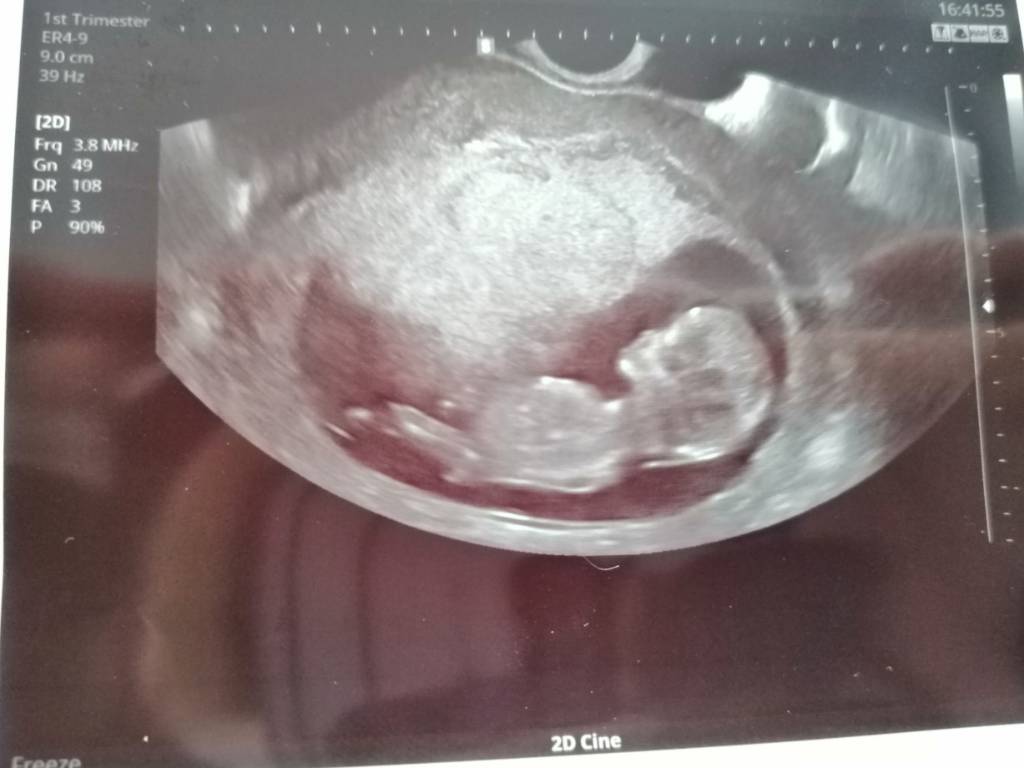

Tylko niepokoi mnie to coś co dostaje, czy to nie nub na chłopca? Lekarz nic nie mówił [emoji12]Zobacz załącznik 1021224